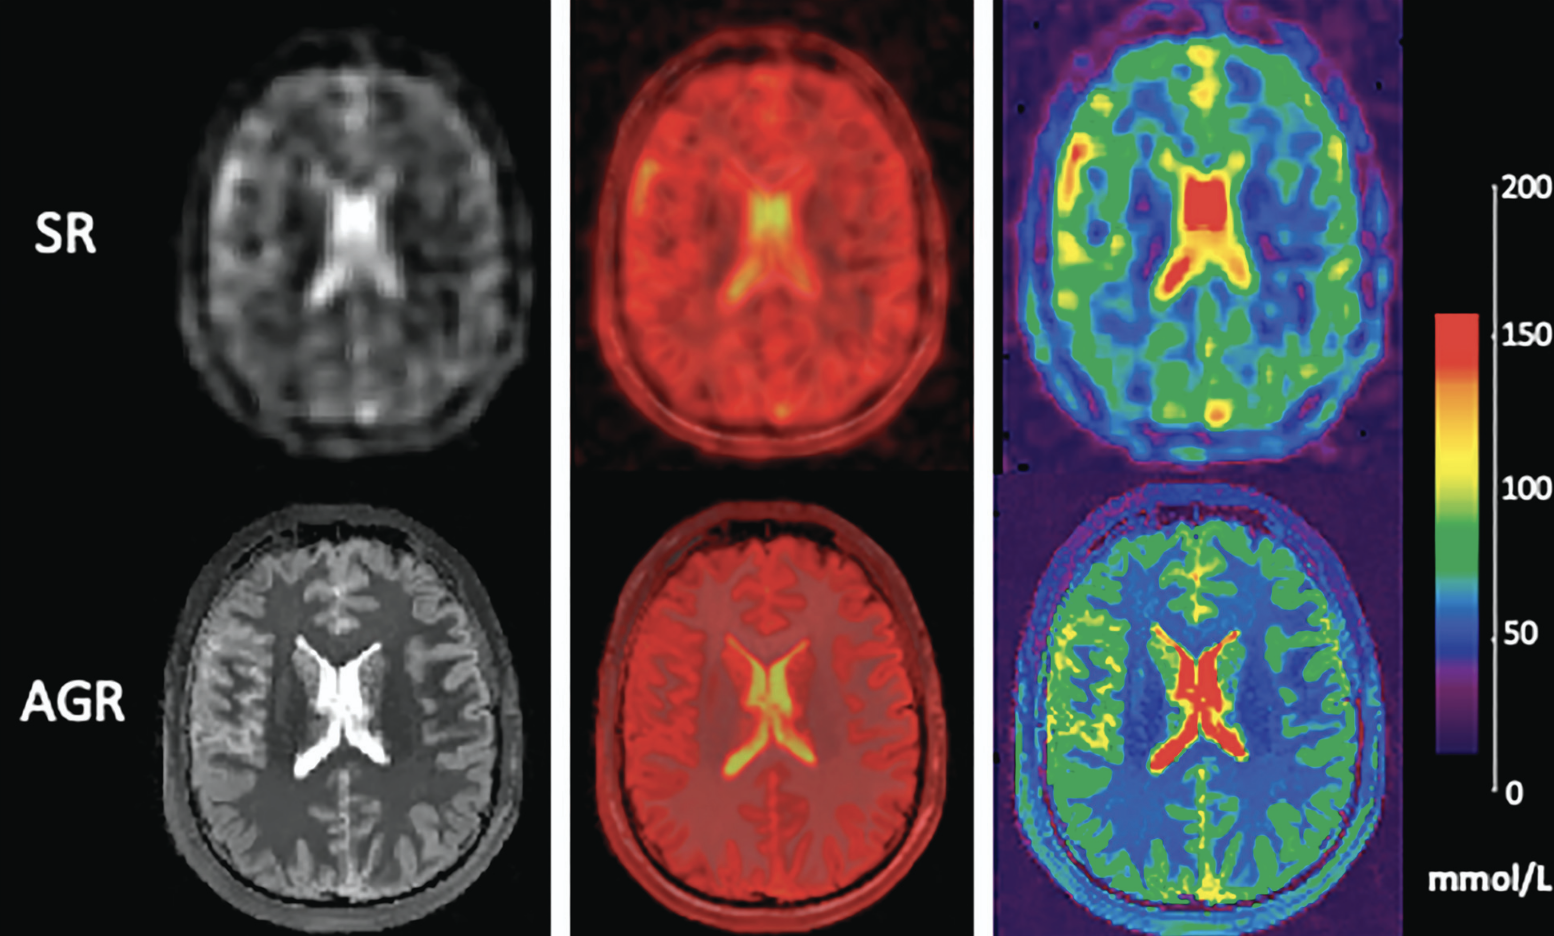

Mapping regional brain total sodium concentration - using anatomically- guided reconstruction of dual echo Sodium-23 MRI: moving toward improved accuracy and precision

Alaleh Alivar, Georg Schramm, Yongxian Qian, and 4 more authors

@article{58,author={Alivar, Alaleh and Schramm, Georg and Qian, Yongxian and Lefer, Hugo and Nuyts, Johan and Boada, Fernando and Lui, Yvonne W.},title={Mapping regional brain total sodium concentration - using anatomically- guided reconstruction of dual echo Sodium-23 MRI: moving toward improved accuracy and precision},elocation-id={ajnr.A8984},year={2025},doi={10.3174/ajnr.A8984},journal={American Journal of Neuroradiology},}

Resolution enhancement, noise suppression, and joint T2* decay estimation in dual‐echo sodium‐23 MR imaging using anatomically guided reconstruction

Georg Schramm, Marina Filipovic, Yongxian Qian, and 4 more authors

@article{52,author={Schramm, Georg and Filipovic, Marina and Qian, Yongxian and Alivar, Alaleh and Lui, Yvonne W and Nuyts, Johan and Boada, Fernando},citation={Magnetic Resonance in Medicine 91 (4), 1404-1418, 2024},doi={10.1002/mrm.29936},journal={Magnetic Resonance in Medicine},number={4},pages={1404-1418},title={Resolution enhancement, noise suppression, and joint T2* decay estimation in dual‐echo sodium‐23 MR imaging using anatomically guided reconstruction},volume={91},year={2024},}